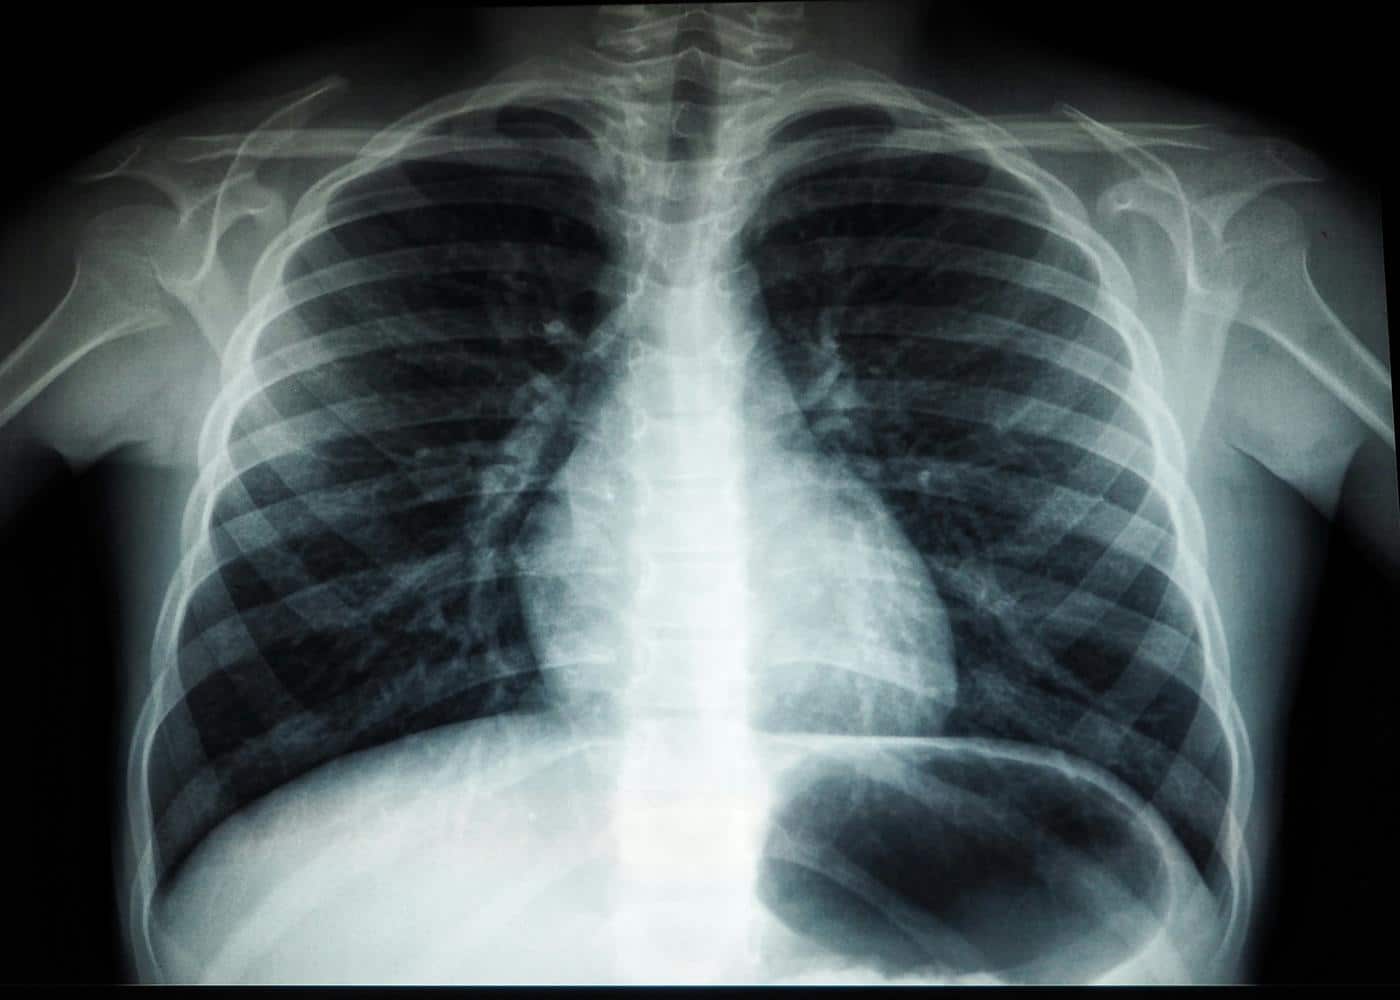

Situated in the upper anterior mediastinum, just behind the sternum and resting precariously over the superior aspect of the heart, the thymus is a primary lymphoid organ with a fascinating developmental trajectory.

To solve this, the investigators turned to the burgeoning field of radiomics and artificial intelligence. They leveraged an enormous repository of routine computed tomography scans, primarily drawing from the National Lung Screening Trial cohort.

This dataset provided high-resolution chest imaging for thousands of adults, coupled with years of rigorous longitudinal follow-up data tracking their health outcomes, disease incidence, and eventual causes of death.

The research team developed and trained a sophisticated deep-learning convolutional neural network to meticulously segment the anterior mediastinum on these scans.

The algorithm was capable of differentiating between functional, dense thymic tissue and the fatty adipose tissue that replaces it during involution. By calculating the ratio of functional tissue to total organ volume, the researchers created a standardized metric of thymic health.

They then cross-referenced these patient-specific thymic health scores against decades of meticulously recorded clinical outcomes, adjusting for an extensive array of demographic and clinical variables. The sheer scale and computational rigor of this approach allowed them to isolate the specific impact of the thymus on adult morbidity and mortality with unprecedented statistical power.

Anatomically, the thymus is situated in the upper anterior chest cavity, occupying a space known as the anterior mediastinum. It lies situated just behind the sternum (the breastbone) and rests directly in front of the superior aspect of the heart and its great vessels, such as the ascending aorta. During infancy and early childhood, it is relatively large and prominent, extending upwards toward the neck. As a person ages, its overall density changes, making it visually less distinct from the surrounding mediastinal fat on traditional imaging, which contributed to its historical neglect in adult medicine.